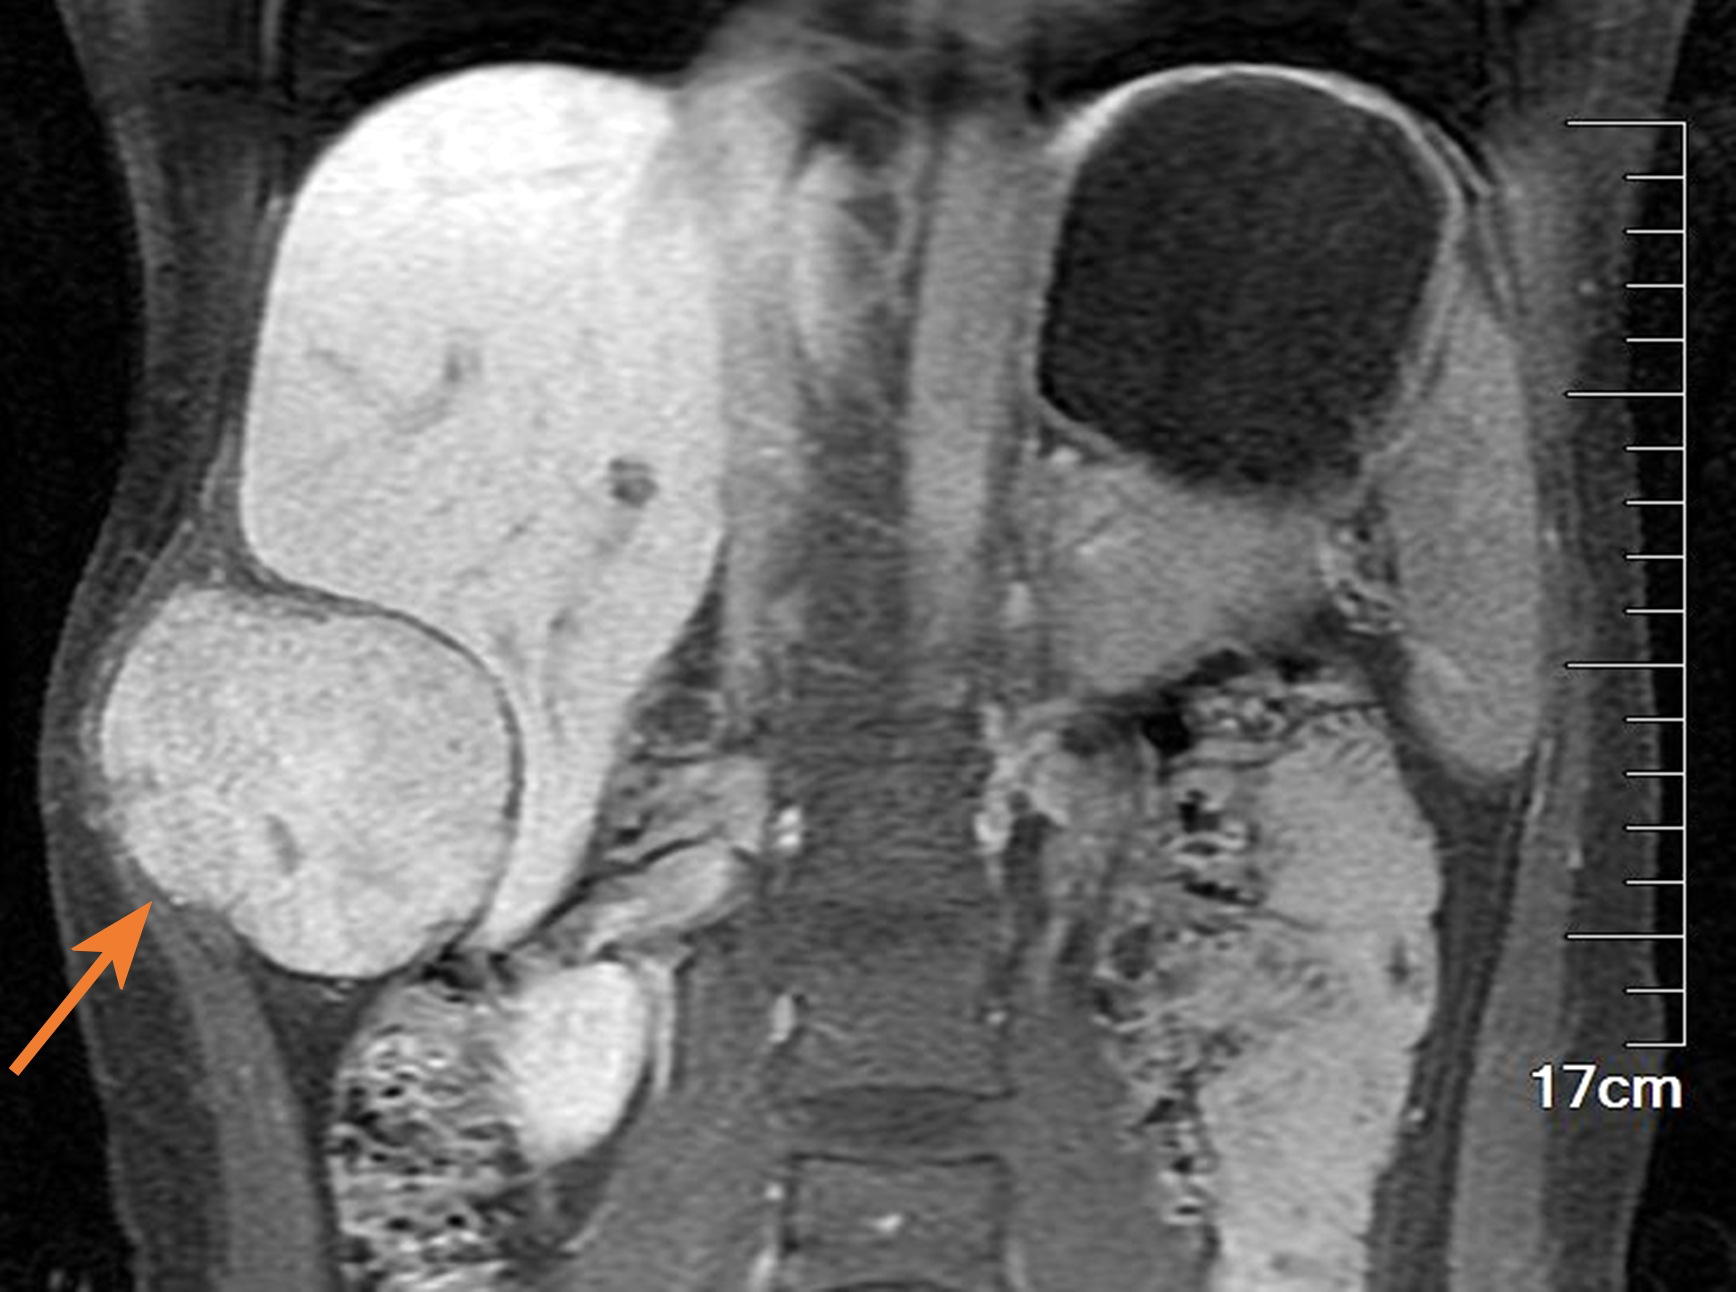

Figure 2

The lump (see the arrow) presented a high signal with a clear boundary between the lump and the lung, but the lump margin was rough and characterized by destruction (MRI T2-weighted images).